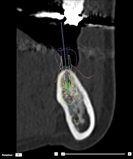

③患者さまの下顎模型のスキャンデータをCT画像と融合(SmartFusion)させることにより、正確なインプラントの位置を確認できます。

④歯列の上からも位置と平行性を確認します。